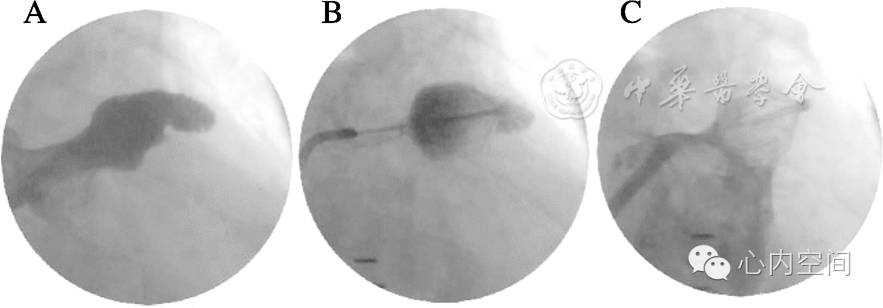

将输送鞘送至左心耳开口处,经与开口垂直的角度进行左心耳造影。然后根据造影结果(图7A)及TEE结果对左心耳口部直径进行测量[26]。再根据左心耳的结构特点,选择尺寸合适的封堵装置(PLAATO封堵器尺寸应比左心耳口部尺寸大20%~50%[53]、WATCHMAN封堵器尺寸应比左心耳体部直径大10%~20%[55],以保证释放后有足够支撑力固定。LAmbre™封堵器(图8)及第2代ACP(图9)[60]目前尚处于临床研究阶段。

除了TEE外,也可通过ICE对左心耳进行测量并指导术者的植入操作。封堵器通过输送鞘送至心耳口部并释放。术中可通过输送鞘进行左心耳造影(图7b)或通过TEE图像来确认封堵器的最佳释放位置。Amplatzer封堵器常置于左心耳较近端的位置,即其着陆点相对较浅,因此以封堵心耳口部为主;而WATCHMAN封堵器的着陆点则相对较远,因此可能受心耳远端或分叶近端复杂解剖结构的影响较大[61]。

左心耳封堵术中左心耳和/或心房造影图

A:穿房间隔后左心耳造影可测量左心耳尺寸;B:经封堵器内腔注射造影剂可通过封堵面后的造影剂染色情况判断位置及封堵情况;C:

如封堵器边缘与心耳组织贴合欠佳或封堵器位置不满意,可回缩封堵器调整后重新膨胀,或保留房间隔穿刺鞘并更换不同尺寸的封堵器。然后测量封堵器的尺寸以确认其膨胀压力是否足够。如压力理想,封堵器尺寸应达到其无压力时的80%~90%。然后需在X线透视下进行手动牵拉并在TEE监视下确认封堵器植入是否稳定。然后释放封堵器,回撤导引鞘管。封堵器释放后,可行左心房造影以确认左心耳完全封堵(图7C)。